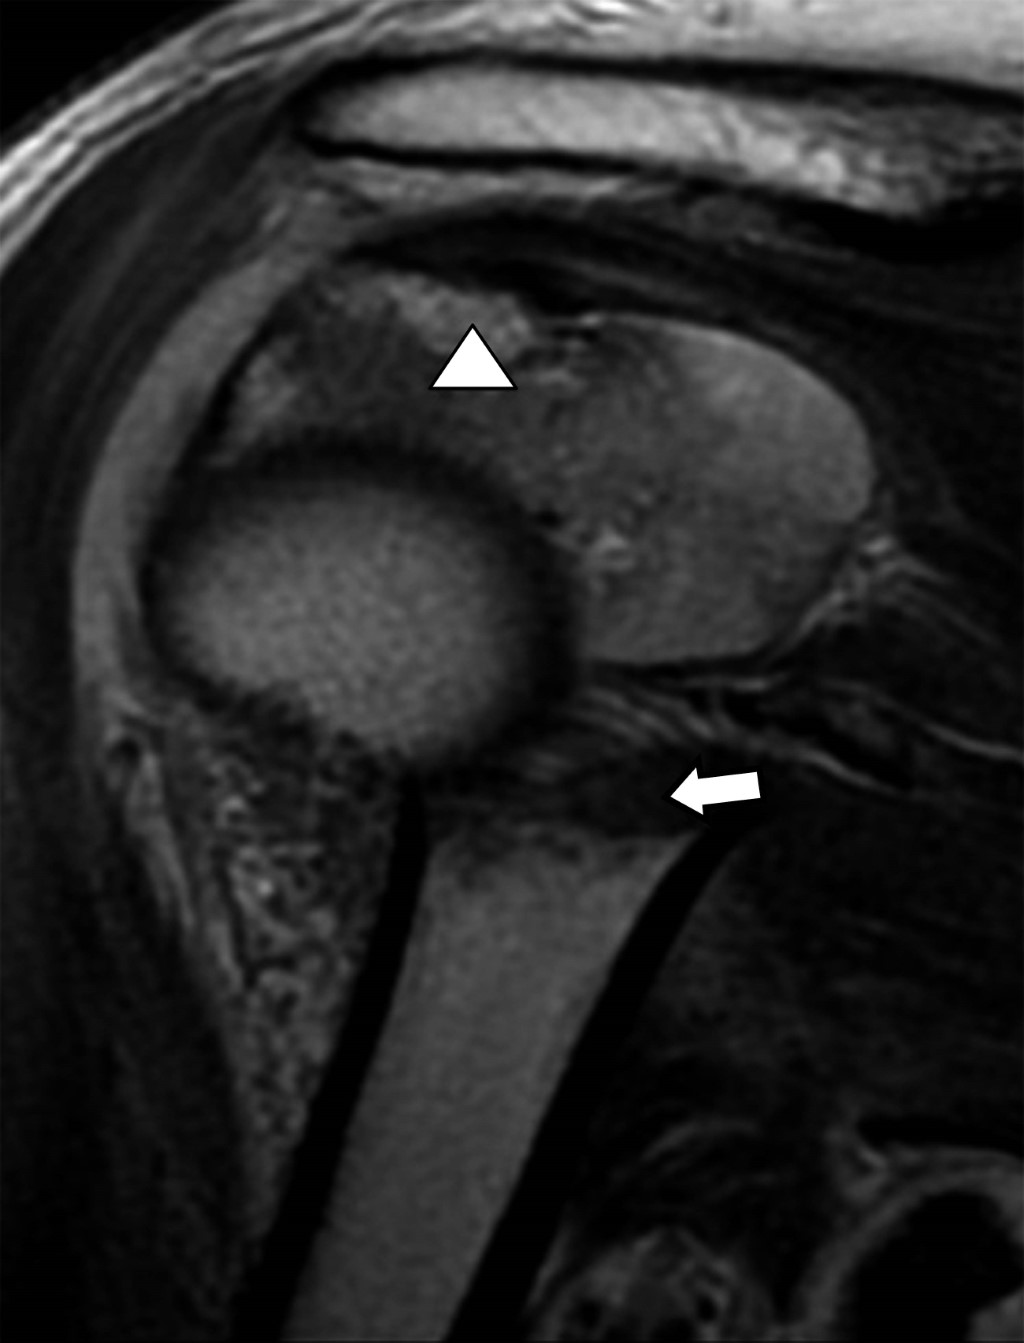

Multifragmentary proximal humerus fracture, the importance of MRI assessment

Proximal humerus fractures represent 45 to 50% of humeral fractures, and the main risk factors are falls, age, osteoporosis, and high-impact sports. The initial diagnostic method for assessing bone structures is radiography, which can be complemented with a tomographic study to assess the fracture line and associated characteristics. In multi-fragmentary fractures with complex lines, the trend of using magnetic resonance imaging is on the rise, as it allows the evaluation of myotendinous and ligamentous structures, which are limitedly evaluated in studies based on ionizing radiation.

Figure 2